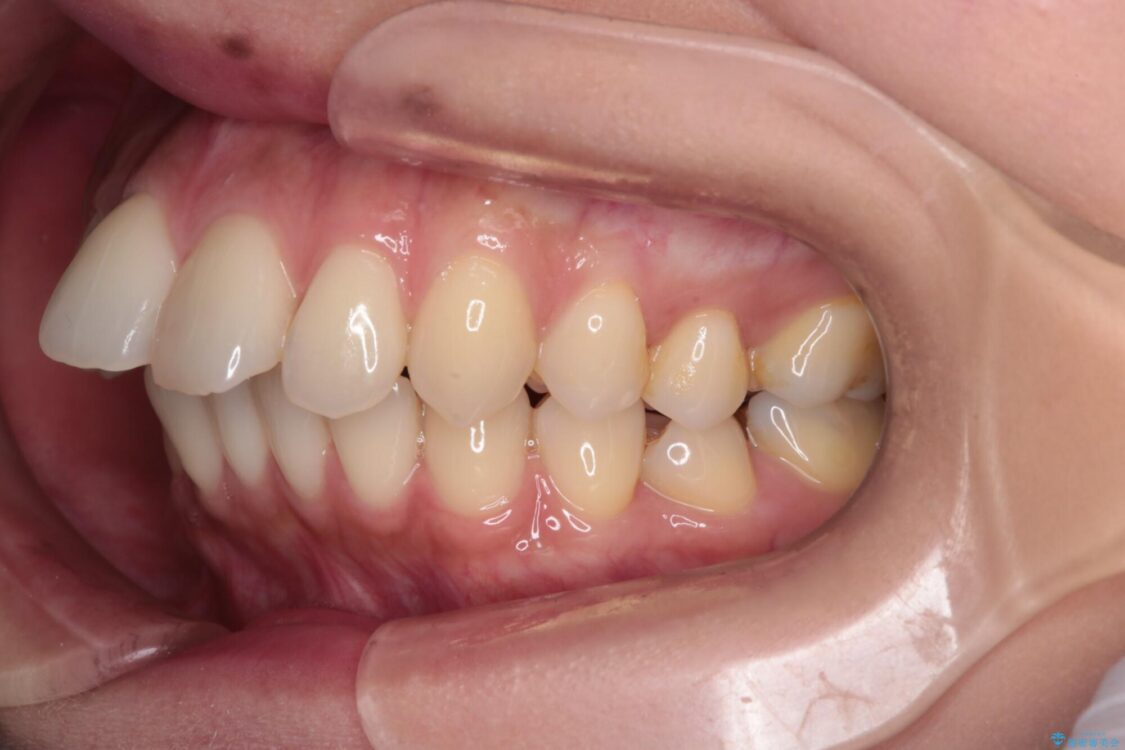

上の前歯の突出感を気にして来院された患者様です。

目立たない装置を希望とのことで、上顎左右第一小臼歯を抜歯し、インビザラインにて矯正治療を行うこととしました。

治療前

• 上顎前歯の突出を軽減 インビザラインによる抜歯矯正 治療前画像